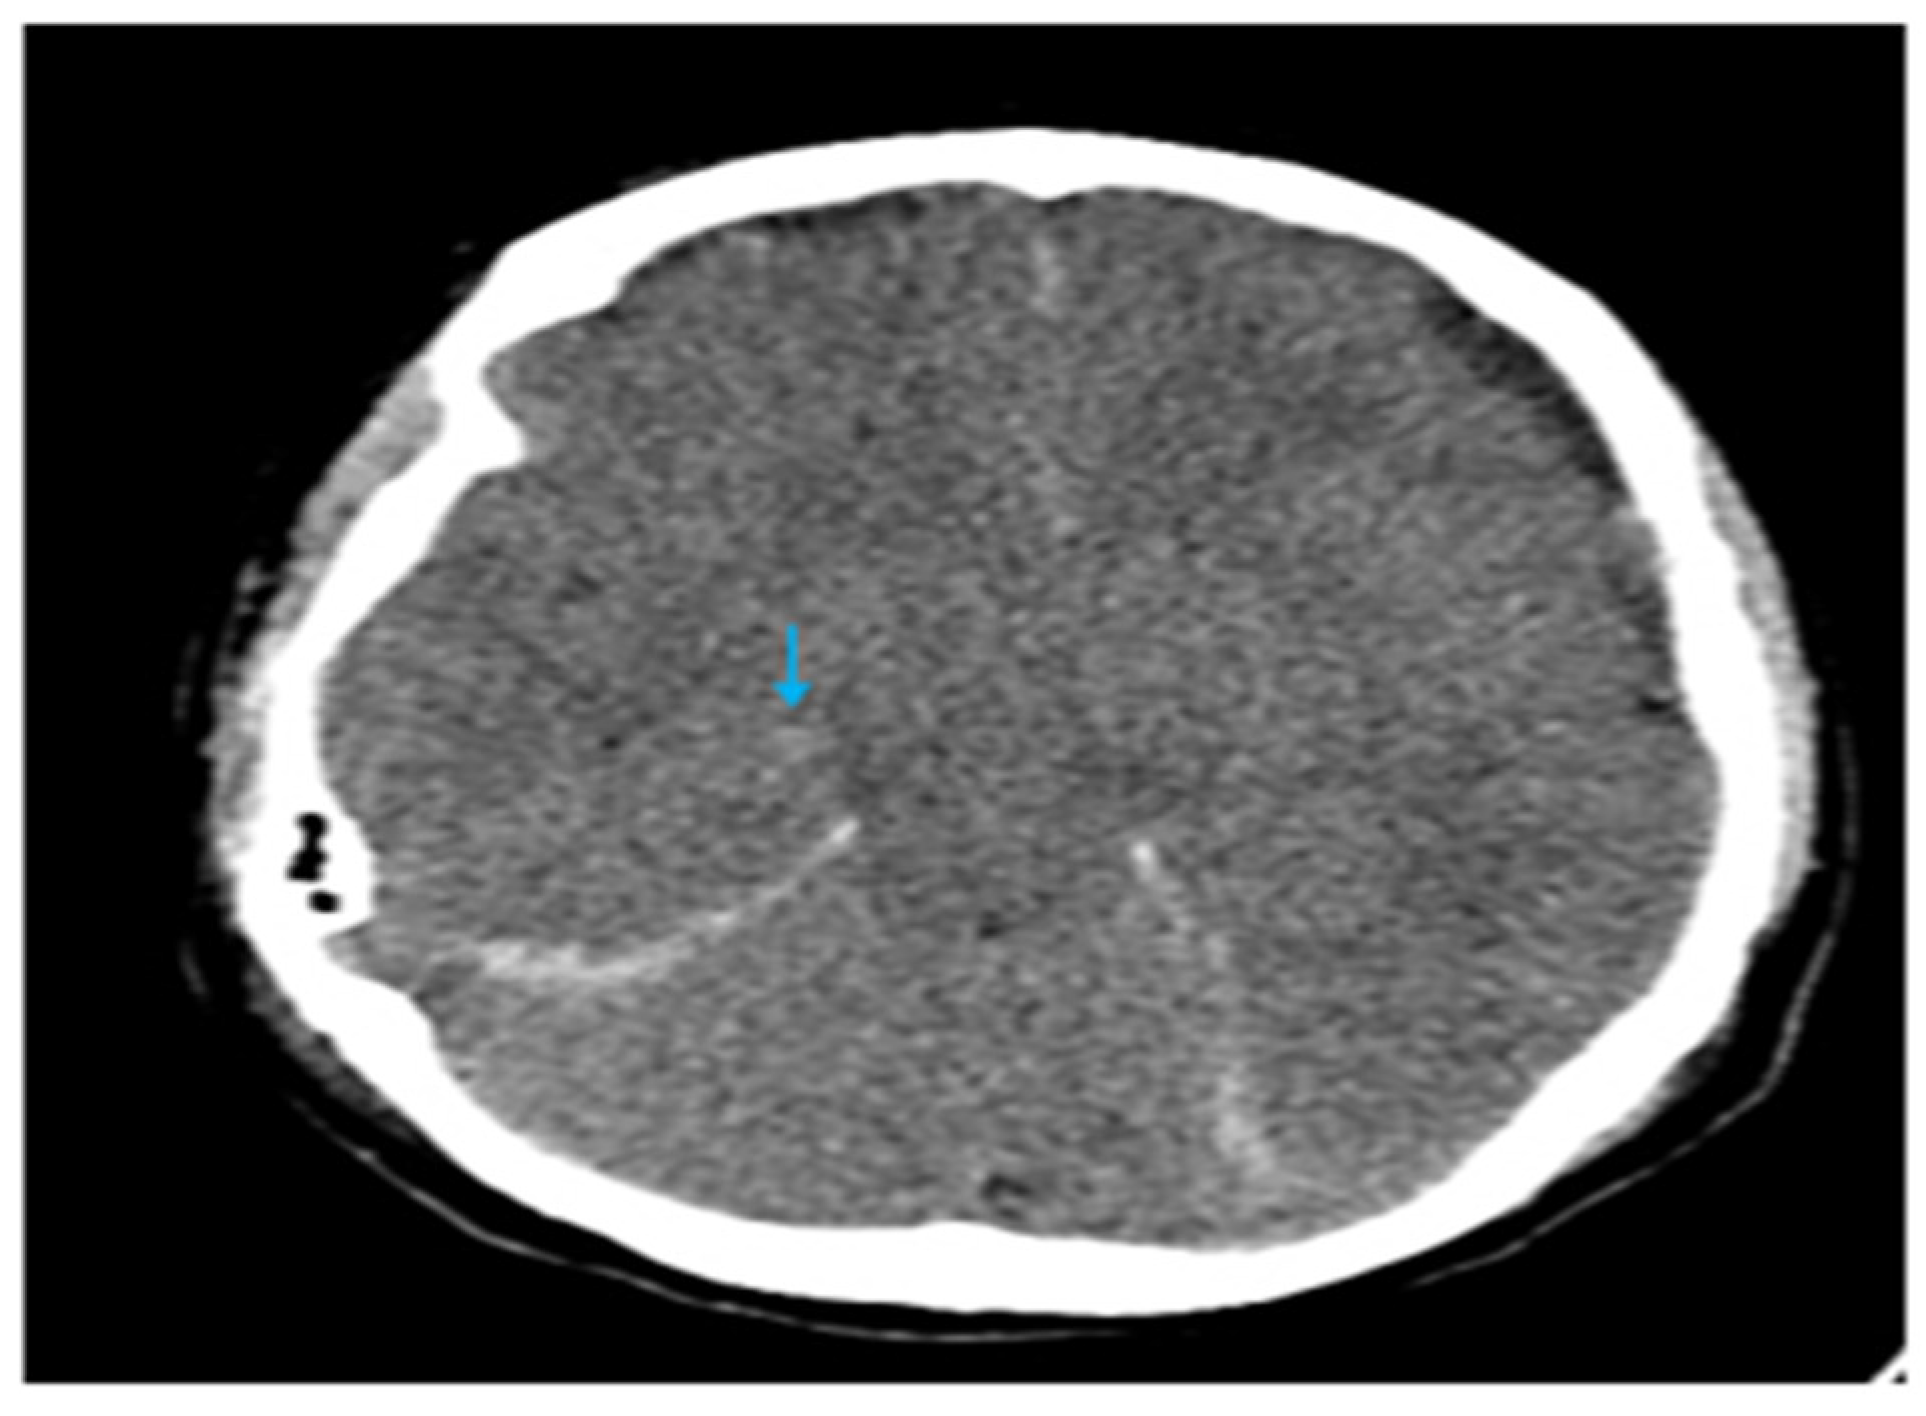

| Database | Search String | Results |

|---|---|---|

| PubMed | (((“Chronic renal failure”) OR (“End-stage renal failure”)) OR (“hemodialysis”)) AND ((“Spontaneous intracranial hypotension”) OR (“Craniospinal hypotension”)) | 1 |

| Scopus | (“Chronic renal failure” OR “end-stage renal failure” OR “hemodialysis”) AND (“Spontaneous intracranial hypotension” OR “craniospinal hypotension”) AND (LIMIT-TO (DOCTYPE, “ar”)) | 20 |

| Dimensions | (“Chronic renal failure” OR “end-stage renal failure” OR “hemodialysis”) AND (“spontaneous intracranial hypotension” OR “craniospinal hypotension”); filter: article | 296 |